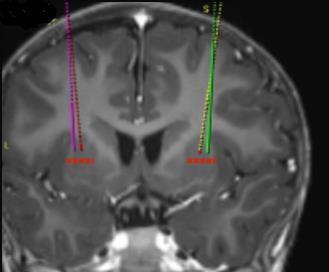

- i siti target di infusione sono definiti secondo lo standard della pratica neurochirurgica stereotassica. Upstaza viene somministrato come infusione bilaterale (2 infusioni per putamen) mediante una cannula intracranica. I 4 target finali per ciascuna traiettoria devono essere definiti come 2 mm dorsale verso (sopra) i punti di destinazione anteriore e posteriore nel piano medio-orizzontale (Figura 1).

Figura 1I quattro punti target per i siti di infusione